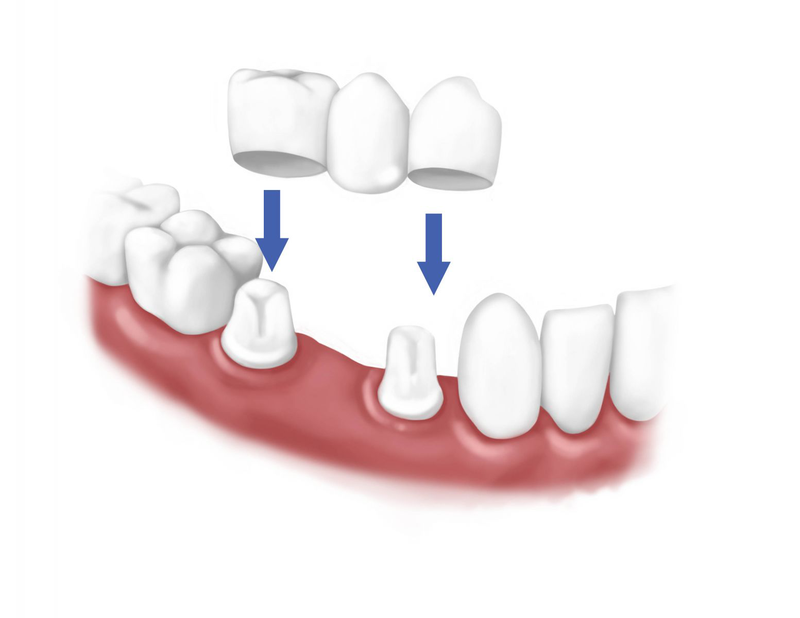

Mất răng hoặc răng gặp phải các bệnh lý ảnh hưởng sinh hoạt và lấy đi nụ cười thẩm mỹ của người bệnh. Ngày nay, để phục